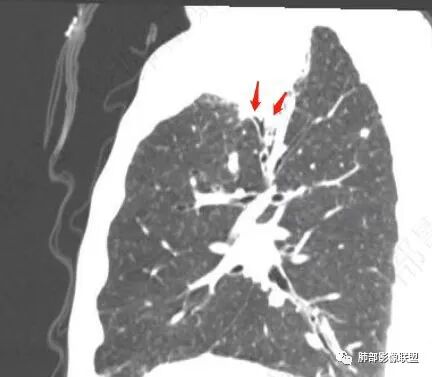

右下叶背段有结节

斑点

主病灶在右上叶尖段、前段纵隔旁,紧贴胸膜

楔形、边缘膨隆,附近见斑片状、网格状高密度影

整体而言:远侧、内侧壁厚

坏死明显,这类膨隆就不支持生长速度不一致所致,而支持坏死朝周围的压力导致边缘的膨隆

这里倒是符合血管的压迫

与胸膜的关系?分界还算清楚